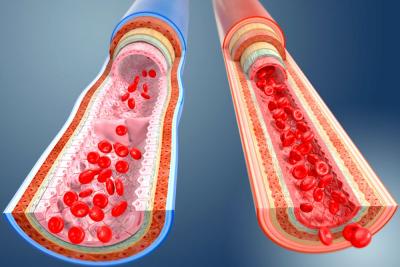

त्यानंतर शरीरातील वेगवेगळ्या अवयवांपर्यंत होणारा रक्तपुरवठा सुरळीत होत नाही. रक्तपुरवठा संथ गतीने होतो. परिणामी किडनी, आतड्यांची समस्या अधिकच वाढत जाते.

हायपरटेंशन, हाय ब्लडप्रेशर, डायबिटीस आणि लठ्ठपणाने त्रस्त असलेल्या लोकांना या आजाराचं संक्रमण जलद गतीने होण्याची शक्यता असते. कारण या व्हायरसने एंडोथिलियम या पेशींच्या कवचाला कमकूवत बनवलेलं असतं.

आरोग्यतज्ञ रुचित्जका यांनी सांगितले की मी आत्तापर्यंत अशा तीन केसेस पाहिल्या आहेत. ज्यात कोरोना रुग्णांच्या रक्तवाहिन्या या व्हायरसने संपूर्ण भरलेल्या होत्या. त्यामुळे शरीरातील अवयवांवर नकारात्मक परिणाम दिसून येत होता.

त्यातील ७१ वर्षीय रुग्णाला हायपरटेंशनची समस्या होती.कोरोना व्हायरसचं संक्रमण झाल्यानंतर शरीरातील विविध भागांनी आपलं कार्य पूर्णपणे थांबवलं. त्यानंतर काही दिवसातच या व्यक्तीला मृत्यू झाला.